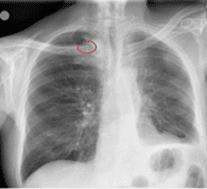

RESULTADOS CLÍNICOS SOBRE LA LÍNEA MEDIOCLAVICULAR

Porcentaje de éxito

A través de su estudio observacional de más de 3 años y cuya muestra es de más de 2800 catéteres, los resultados fueron muy positivos:

“El porcentaje de éxito respecto a la inserción es de 99,3% y se ha realizado en una sola punción en el 92,7% de los casos. Hay que tener en cuenta que el porcentaje de pacientes DIVA en nuestra área es del 73,7%.

Contemplando el catéter en toda su duración, su éxito fue del 83,2%.””

Complicaciones

Las retiradas inesperadas representan el 16,8% y como excelente resultado está la tasa de complicaciones: para una media de 21 días de duración por catéter, no hubo incidencias de infiltración ni de flebitis y los casos de trombosis y bacteriemia fueron muy pocos.

Las complicaciones más recurrentes fueron la retirada accidental (6,1%) y la obstrucción (2,5%).

COMPARACIÓN CON OTROS TIPOS DE CATÉTERES

Según su experiencia, comparado con el mini-midline y el PICC, cabe destacar que la línea media subclavia es el DAV con mejor tasa de éxito.

La tasa de trombosis de este catéter es la más baja de las 3 categorías mencionadas e incluso más baja que lo comentado en la literatura.